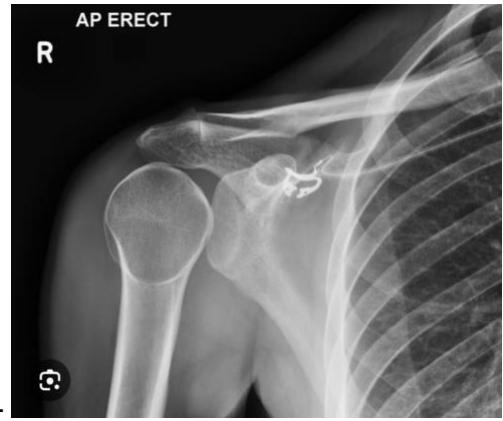

Anterior Shoulder Dislocation

What is the diagnosis shown in the image?

- Anterior Shoulder Dislocation

What is the most common complication of anterior shoulder dislocation?

- Axillary nerve injury

Hill-Sachs Lesion

What does this photo show?

- Hill-Sachs lesion

18-year-old male presented after sport injury and unable to do internal rotation of right shoulder. What is the name of the injury seen in the figure?

- Hill-Sachโs defect

18-year-old male presented after sport injury and unable to internally rotate his left shoulder. What is the diagnosis?

A case scenario about a male with anterior shoulder dislocation. What does the figure 1b show?

reverse - Hill sachs lesion

What do you see in this image?

- Hill sachs lesion

Associated Injuries

What is the associated injury in anterior shoulder dislocation?

- Lesser tuberosity fracture

18-year-old male presented after sport injury and unable to internally rotate his left shoulder. What is the likely finding?